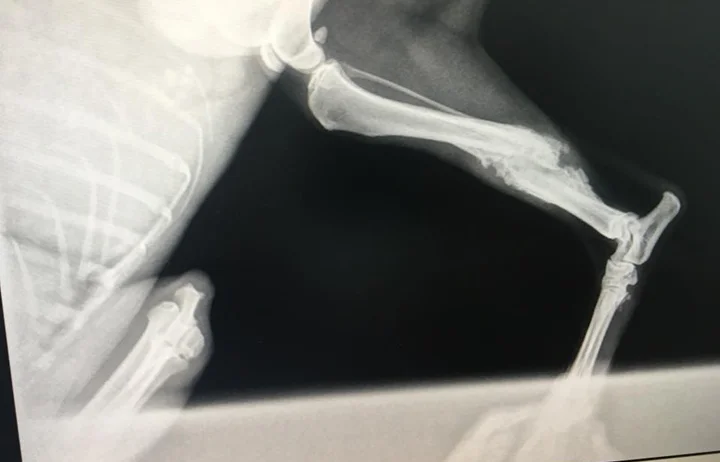

Leg break

Carrot was found her on the side of the road. We believe she had been hit by a car — her face was scraped, bleeding and swollen with broken front teeth. Her leg had also been broken at some point but it is too late to operate. She’s tiny, weighing just 7-9kg. Carrot is very scared but that’s to be expected. She is relaxing in the kennels and catching up on her sleep and eating. Please contact us for more information.